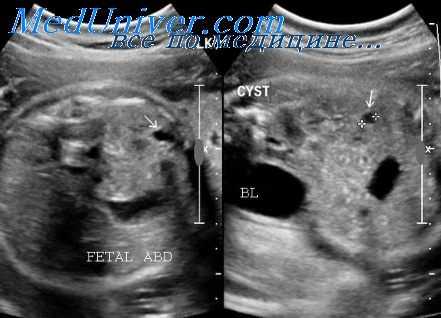

Независимо от причины обструкции, при ультразвуковом исследовании мочевой пузырь будет расширенным и с утолщенными стенками. Задний отдел мочеиспускательного канала может быть расширен и выглядеть как основание мочевого пузыря, особенно при наличии заднего уретрального клапана. Мочеточники в этих случаях также обычно расширены.

Вид почек будет различным в зависимости от наличия дисплазии и ее степени. Возможны гидронефроз при нормальной паренхиме почки, гидронефроз с эхогенной или кистозной паренхимой или небольшие сморщенные почки с гиперэхогенной паренхимой. Почки также могут выглядеть нормальными или иметь незначительно выраженный гидронефроз в случаях, когда происходит разрыв стенки мочевыводящего тракта и наступает его декомпрессия.

При этом в околопочечном пространстве или в брюшной полости плода будет определяться свободная жидкость. Такое состояние носит название мочевого асцита.